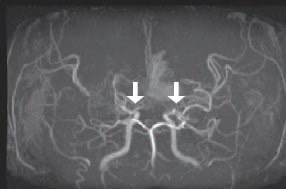

모야모야병은 뇌기저부의 주요 혈관이 서서히 협착되고 막히면서 뇌혈류가 감소하는 만성 진행성 뇌혈관 질환입니다. 협착이 진행된 부위를 대신해 뇌는 생존을 위해 얇고 약한 혈관망을 만들어 혈류를 보충하려 하고, 이 새로운 혈관들이 촬영 영상에서 연기처럼 퍼져 보인다고 하여 ‘모야모야’라는 이름이 붙었습니다. 기전적으로는 내경동맥 말단부와 중대뇌동맥·전대뇌동맥의 기시부에 병변이 가장 잘 생기며, 시간이 지남에 따라 양쪽에 대칭적으로 나타나는 특징을 보였습니다. 이 질환은 단순한 혈관 협착이 아니라 진행성 변화이기 때문에 치료하지 않으면 혈류 부족이 심해지고 뇌 손상이 누적될 수 있습니다. 또한 뇌기능이 체력·호흡·체온 변화 등에 민감하게 반응하기 때문에 과호흡, 울음, 격렬한 운동, 감염 등으로 증상이 악화될 수 있습니다. 즉, 모야모야병은 시간이 지나면서 뇌혈류를 감소시키고 뇌졸중 위험을 높이는 질환이며, 평생 관리가 필요한 만성적 특성을 갖고 있습니다.

따라서 가족력이 있거나 의심되는 증상이 있다면 뇌 MRA·MRI 등의 정기검진이 도움이 되며, 조기 진단 시 치료 효과도 훨씬 높아집니다.